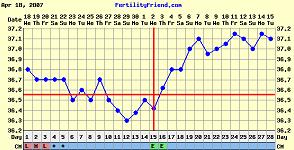

Bettike, tök jó végre tőled egy ilyen szép görbét látni a hiperciklusaid után!

És nagyon simogattyajakicsiszivemet, hogy az én babás görbém ilyen példaértékű. Úgyhogy Bonikám, tiád a pálya, úgyis utálom, hogy mindig az én hsz-om az utolsó a másik hőmérősben.